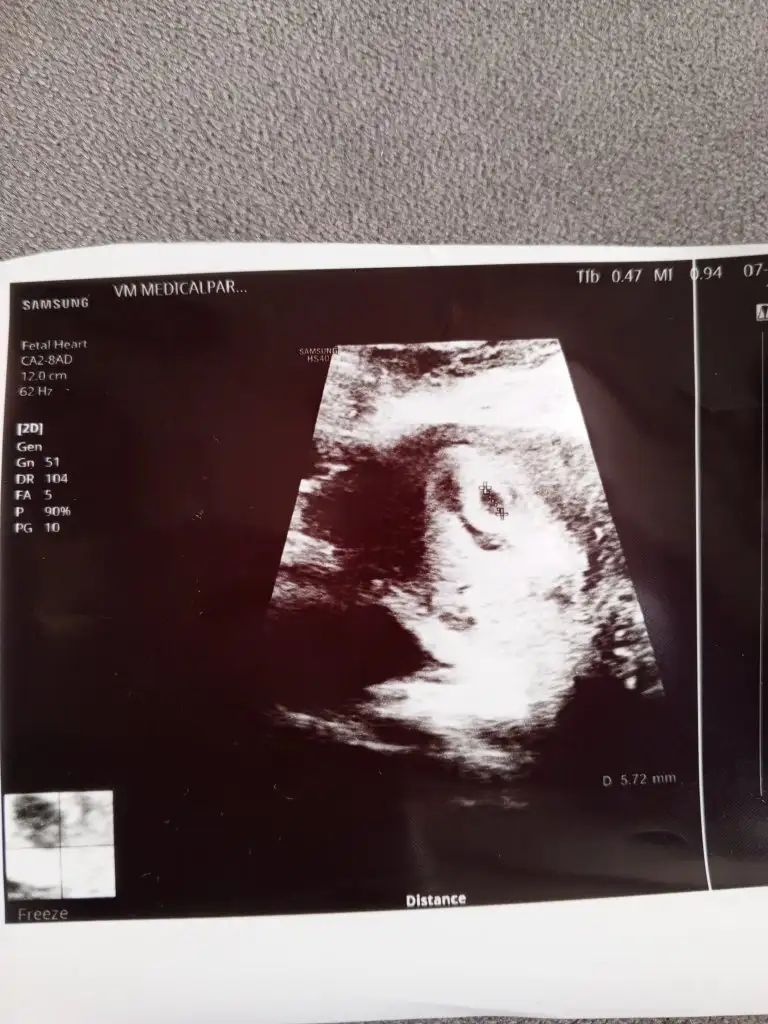

gidiyim o zaman 2-3 gün sonraCanım 1500 olunca vajinal ultrason ile görünüyormuş bikaç gün sonra normal ultrason ile görebilirsin hayırlı olsun![]()

Yaa tamam canım 2 güne görünür o haldeGözün aydın canım. Bana da doktor hiç progesteron bakmadı içini ferah tut. 3000 ile 5000 arasında ultrasonda görünür demişti doktorum bana

Görünebilir bence canım salı günü 3.500 gibi bir şey oluyor betanKızlar benim betam da dün 446 çıktı Salı günü gidicem doktora ama kese görünür mü görünmez derseniz acaba erteleyeyim mi bu arada bugün 4+3

Görünür canım büyük ihtimalleYa ben de en son 1300 çıkmıştı beta cumartesi yaptırmıştım bir daha gitmedim gerek yok demişlerdi, tüp bebek olunca hesaplamalarda 5+1 görünüyor cumartesi keseye gideceğim görünür di mi ya acaba vajinal mı bakar yoksa normal mi ?